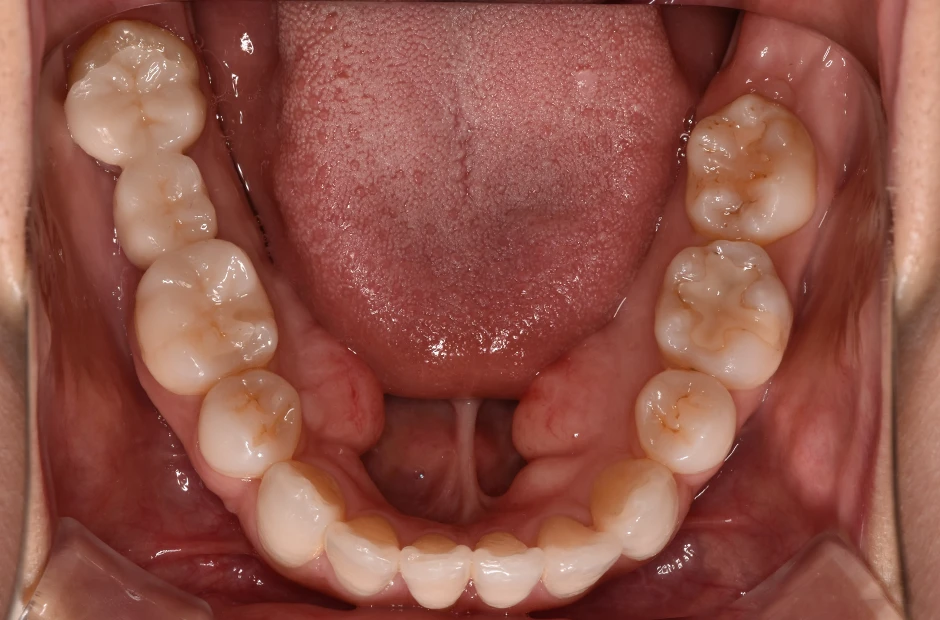

治療前

治療中

治療後

叢生

| 診断名・主訴 | 叢生 |

|---|---|

| 年齢・性別 | 43歳・女性 |

| 治療期間・回数 | 2年7か月 27回 |

| 治療に用いた主な装置 | 舌側矯正 |

| 抜歯部位 | 両顎4,4 |

| 治療費 | 100万円(税抜) |

| リスク・副作用 | 装置による違和感・疼痛・歯肉退縮・歯根吸収・虫歯のリスクなど |